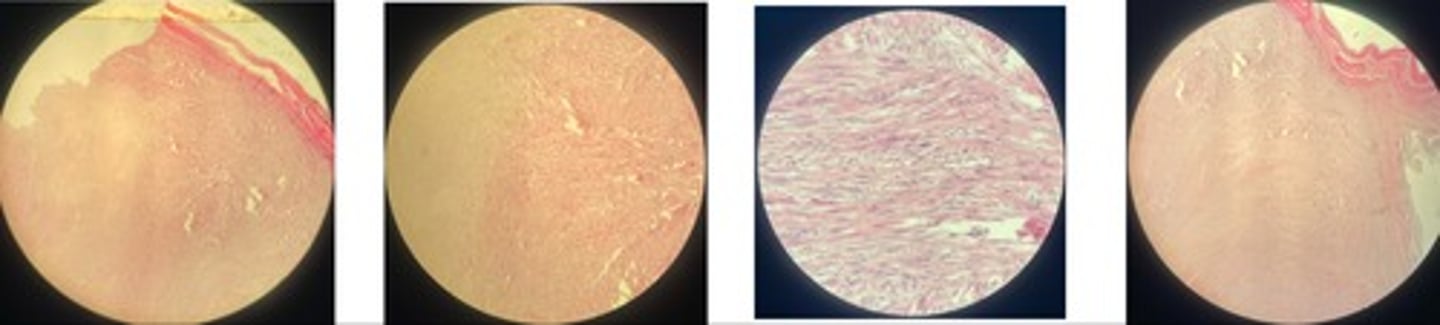

Fibroma

- whorls + interlacing bundles of fibroblasts, fibrocysts, collagen fibres

- may be firm or soft

- soft => fibromyxoma… collagen mixed w/ mutinous ground substance

Fibrosarcoma

- highly vascular but poorly formed

- interwoven ⭐️ immature fibroblasts

- collagen fibres

- nuclei elongated + mitotic figures

Feline injection site sarcoma FISS

- neoplastic spindle cells separated by fibromyxoma matrix (soft!)

- nuclei elongated + mitotic figures

- area of necrosis

- multinucleated giant cell